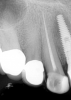

Fig 7. Primary endodontic and secondary periodontal lesion, mandibular second molar.

Figure 7

In Figure 7, the periapical radiograph identifies the presence of the combined endodontic-periodontal lesion developing due to a carious lesion beneath an existing vintage gold crown with ill-fitting margins. Intraoral examination revealed a fistula developing and moderate pain on percussion and mastication. After occlusal access and clear visualization of the canals, the canals were shaped using the rotary files, with precautions taken not to perforate or enlarge the apical foramen. Maintaining the endodontic therapy within the canals prevents the infection from being introduced into the surrounding periodontium. In this case, calcium hydroxide medicament was placed into the canals and evaluated 30 days postoperatively.8

The patient returned for final evaluation of the provisional calcium-hydroxide endodontic therapy and resolution of the infection (33 days postoperatively). Fistula was not present; the tooth was not sensitive to percussion or mastication. The gold crown was removed using a high-speed metal cutting bur, the remaining caries were excavated conservatively, and the endodontic therapy was completed. Placement of glass-fiber reinforced composite and composite core buildup took place. The natural tooth structure to receive the glass-fiber post and a long-term restoration was available (Figure 8). Within one appointment, the tooth was restored (Figure 9). The patient was instructed to return for clinical and radiographic evaluation after 6 to 12 months to determine progression of periodontal healing. At that time, if the healing were adequate and the tooth were stable, evaluation of the tooth would be considered every 3 to 4 years.7